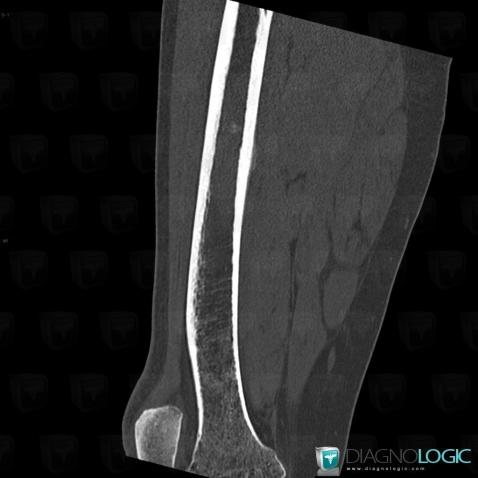

Ewing sarcoma, Femur - Mid part, CT

Here is the specific information in the key image above:

- Diagnosis Ewing sarcoma, Location(s) Femur - Mid part, with gamuts Localised periosteal reaction, Asymmetric periosteal reaction